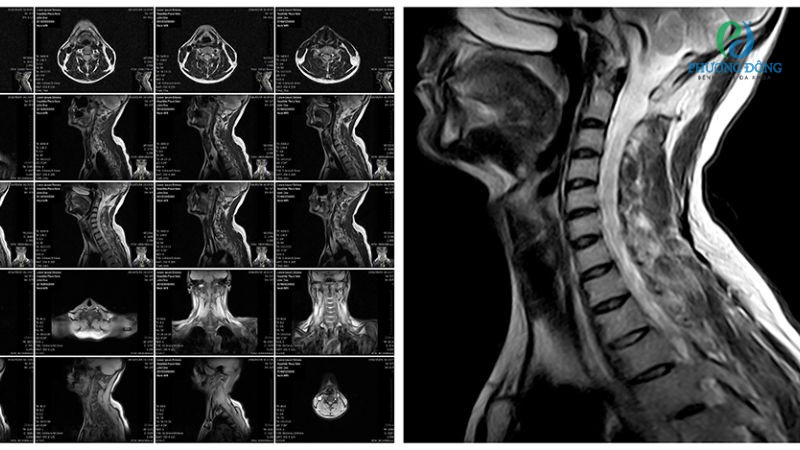

- Chụp MRI giúp xem xét kỹ hơn các phần tổn thương bên trong xương, mô mềm xung quanh như dây chằng, đĩa đệm, các mô mềm khác.

- Chụp CT-Scan quan sát các tổn thương tại xương và cấu trúc xung quanh, tuy nhiên không phù hợp với người từng đặt máy tạo nhịp.

Phương pháp chẩn đoán tình trạng hẹp lỗ liên hợp cột sống